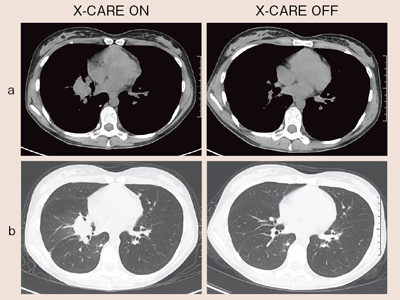

●胸部単純CTの症例提示

図6aは乳頭部レベルにおける縦隔条件の画像,図6bは肺野条件の画像である。どちらもX-CAREを用いても目立ったアーチファクトはなく,診断に問題のない画像が得られている。両側乳房と心臓,および背面の筋肉にROIを置いてSD値を測定したところ,X-CAREのONとOFFで有意差は認められなかった。

図6 胸部単純CT(17歳,女性)